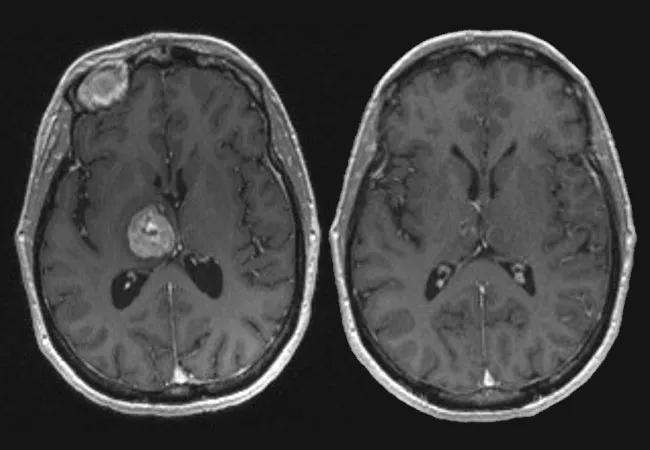

MRIs from a patient who underwent staged Gamma Knife therapy. Top images are before the first session (left) and immediately before the second session (right). Bottom images are from six months (left) and four years (right) after the second session, where significant reduction in the size of the metastases can be seen.

Indeed, among Cleveland Clinic’s first 54 patients — with a total of 63 brain metastases 2 cm or larger — the local control rate at six months has been 88 percent. That compares with a prior local control rate of 49 percent for similar-sized brain metastases treated with single-stage Gamma Knife therapy at Cleveland Clinic.

The median time between treatments in these 54 patients was approximately one month. In many cases, the tumor decreased in size markedly enough so that the second stage of treatment was able to deliver a lower radiation dose to regions adjacent to the tumor, thus better protecting the surrounding normal brain tissue.